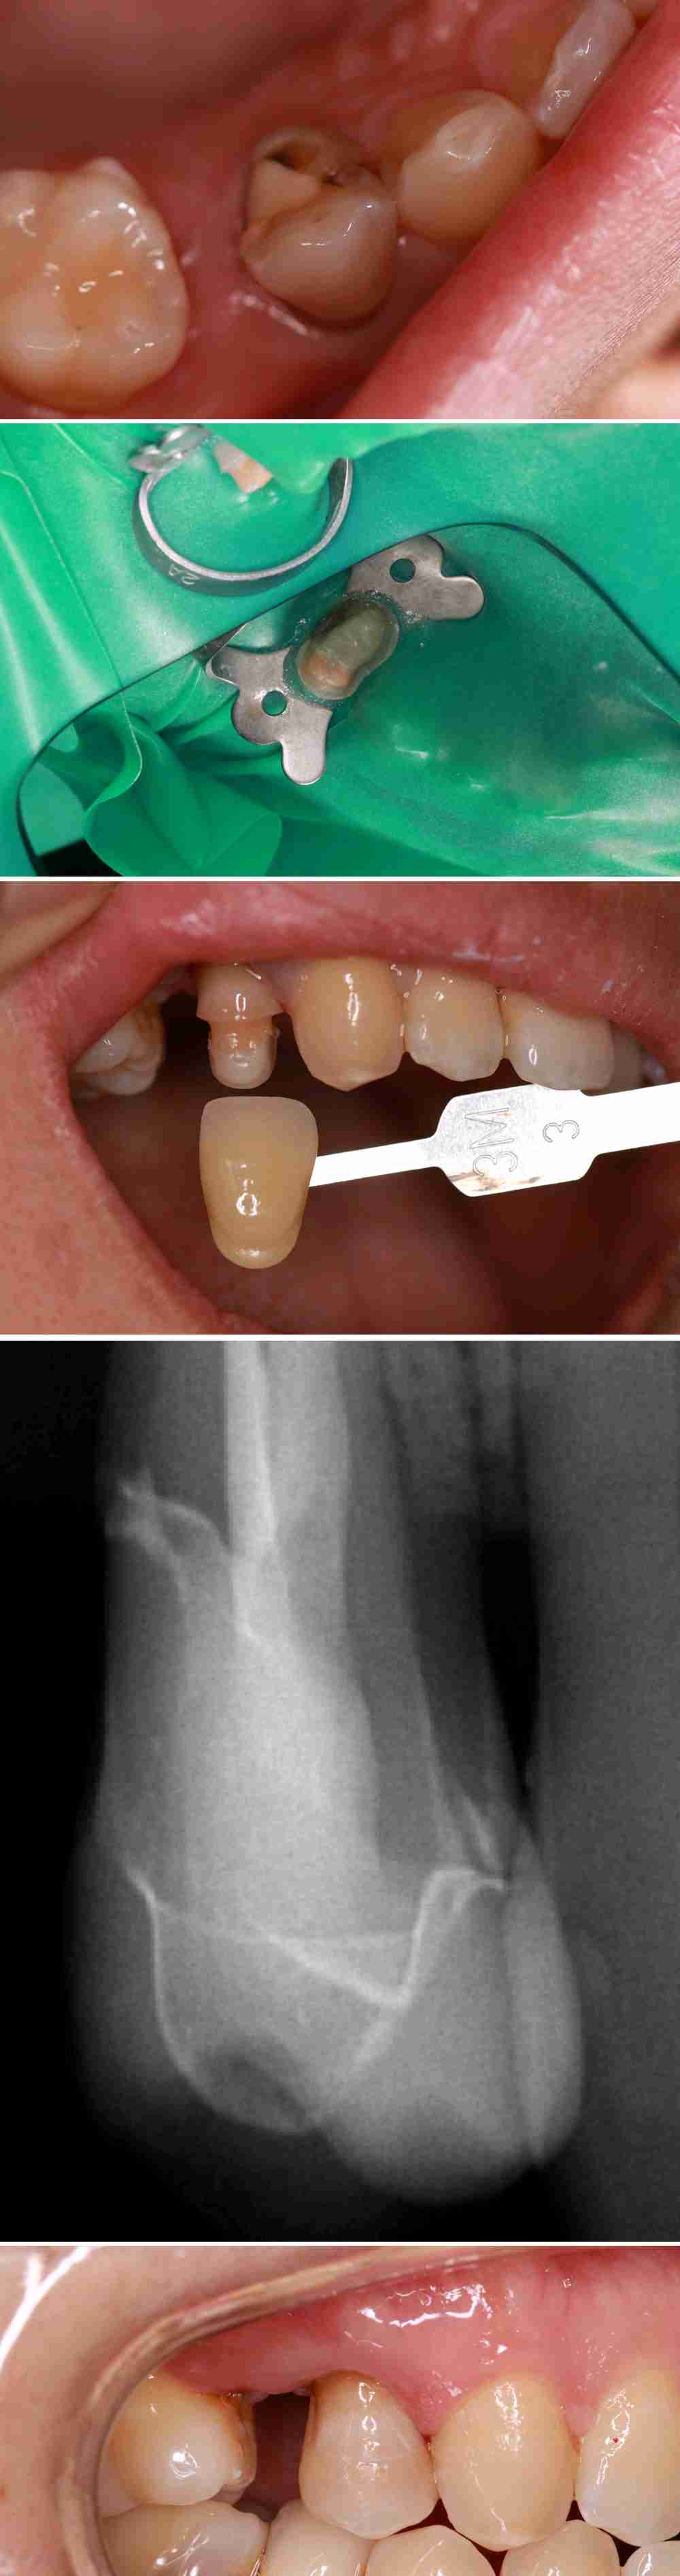

优点:经济实惠。

缺点:

第一个:因树脂会释放游离酸,深龋术后酸痛的感明显。

第二个:容易形成充填物悬突,术后出现食物嵌塞,致牙龈红肿。不适。

第三个:因树脂聚合收缩反应,数年后边缘,出现继发龋。

(上图继发龋)

(上图边缘不密合,酸痛,继发龋)